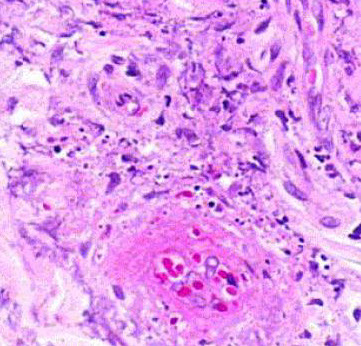

Micro: atypical vascular spaced lined by endothelial cells c atypia and multilayering that involves subQ and has RBCs in intracytoplasmic lumina in more solid areas

- lots of mits and necrosis

Bland-appearing angiosarcoma with multilayered endotheliom that infiltrates (splits) through collagen

Angiosarcoma can have more solid, spindly areas